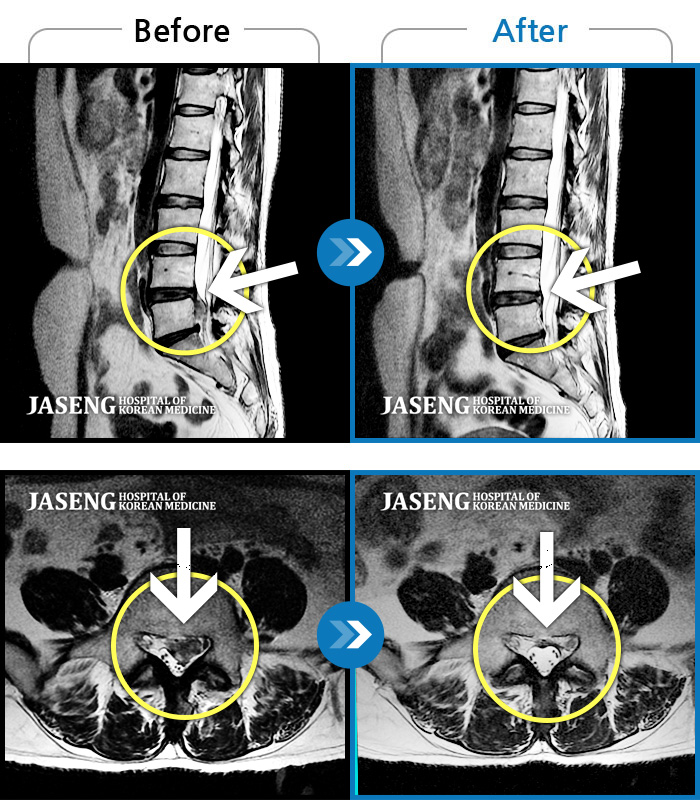

허리디스크

대전 · 김창연 원장

허리통증이라 왼쪽 발목~발등이 저려요. 엄지발가락에 힘빠지는 느낌, 전기오는 느낌이 있어요.

촬영시기

2023.07.17 ~ 2024.07.26

2024.08.09